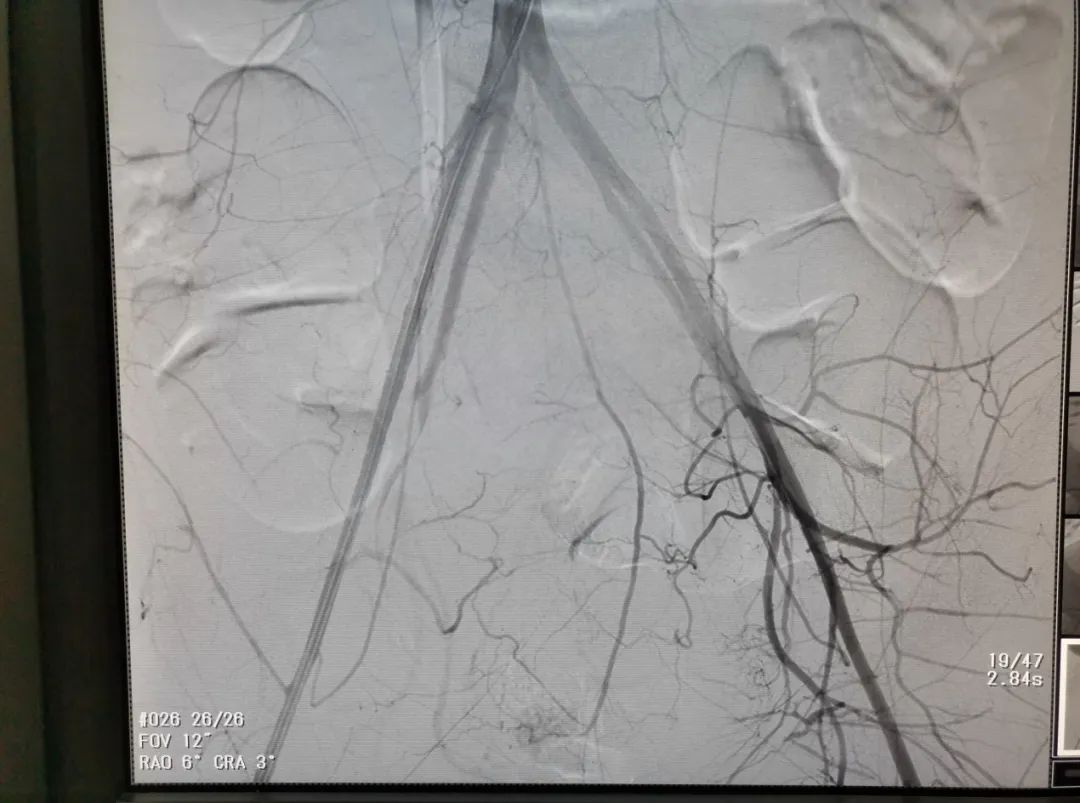

明确出血部位后行超选择性双侧子宫动脉栓塞术。造影下见栓塞满意,如图2:

2超选择性子宫动脉栓塞术后

患者术后阴道流血停止,避免了开腹切除子宫止血,保留患者生育能力,目前患者术后恢复好,顺利出院,术后随诊正常。